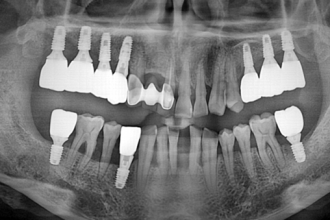

임플란트